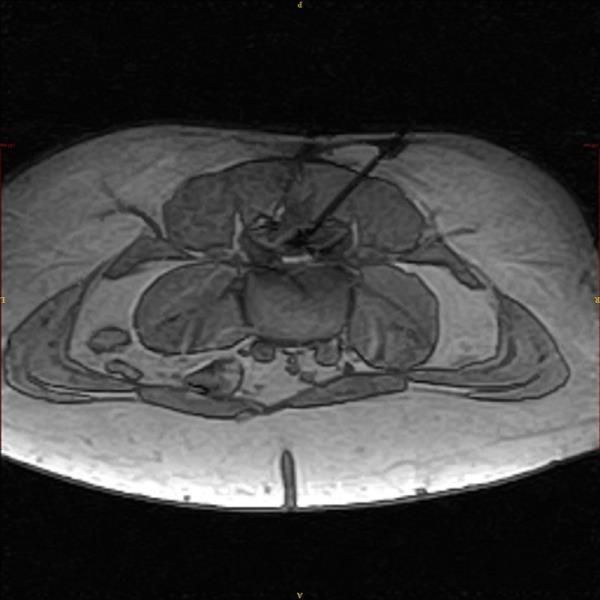

Wie wird die MRT-gesteuerte PDI-Therapie durchgeführt? Bei der MR-gesteuerten Schmerztherapie handelt es sich um ein besonders präzises Verfahren. So werden per kernspintomographischer Planung in Bauchlage des Patienten feine Nadeln millimetergenau an die schmerzenden Strukturen wie Wirbelgelenke oder Nervenwurzeln sowie ggf. auch an einen Bandscheibenvorfall herangeführt. Nach Kontrolle der Nadellage werden z.B. die Wirbelgelenke infiltriert oder aber eine Nervenwurzel mit betäubenden und entzündungshemmenden Medikamenten umspritzt. Selbstverständlich erfolgt vor jeglicher Therapie eine präzise Analyse des Schmerzes durch die genaue Befragung des Patienten zu seinem Schmerzbild. Anschließend werden diese Befunde mit den Ergebnissen einer kernspintomographischen Untersuchung (MRT) verglichen. Konventionelle Röntgenuntersuchungen haben hier nur eine sehr begrenzte Aussagekraft.